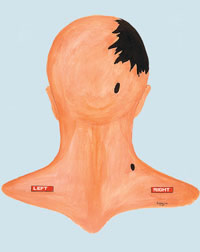

That's what "photo experts" like Robert Groden (in The Killing of a President, page 81) and Harrison Livingstone (in High Treason II) do. Wanting to show the back of Kennedy's head blown out — and thus push the notion of a Grassy Knoll shooter — they use a close-up autopsy photo of the inside of Kennedy's skull after the brain was removed. By rotating the photo ninety degrees clockwise, they can make it appear that the photo shows a large defect in the back of Kennedy's head. In actuality, Kennedy was photographed from the front, and the photo shows the top if his head blasted out, as shown in this drawing by Dr.

Robert Artwohl. Finally, a large and properly-oriented copy of the head photo.